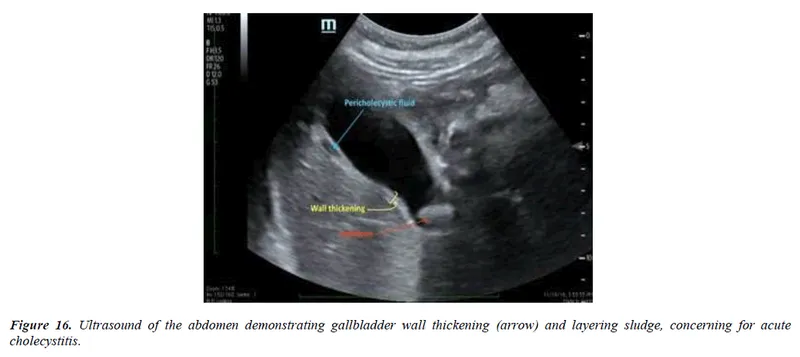

- USG: Wall thickening >3 mm, pericholecystic fluid, sonographic Murphy's.

⭐ Sonographic Murphy's sign is highly specific for acute cholecystitis.